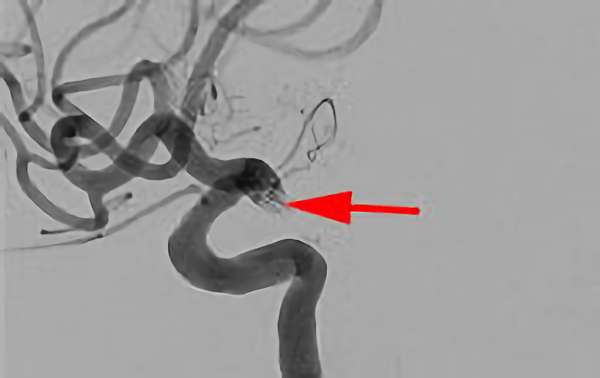

No.1600 手術前

No.1600 手術中

No.1600 手術後

くも膜下出血

脳底動脈瘤破裂

40代

救急外来